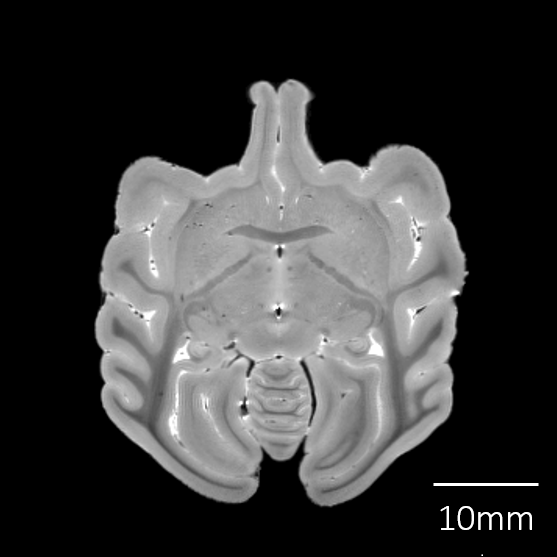

個体・脳標本情報

| 剖検番号 | Pr6182 |

性別 |

オス | |

死亡時年齢 |

1才 | |

| 死亡時体重 | 600g | |

| 脳重量 | 49.9g | |

脳標本画像

| T2強調画像 |